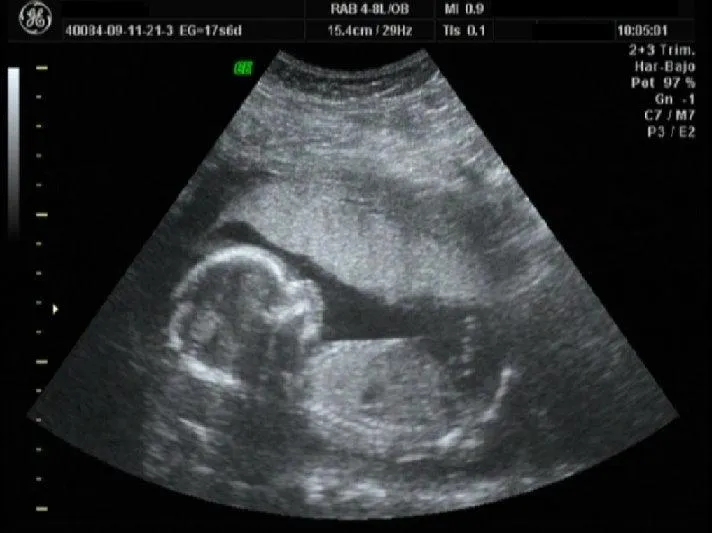

El Blog De Santiago Emiliano..: Segundo Ultrasonido